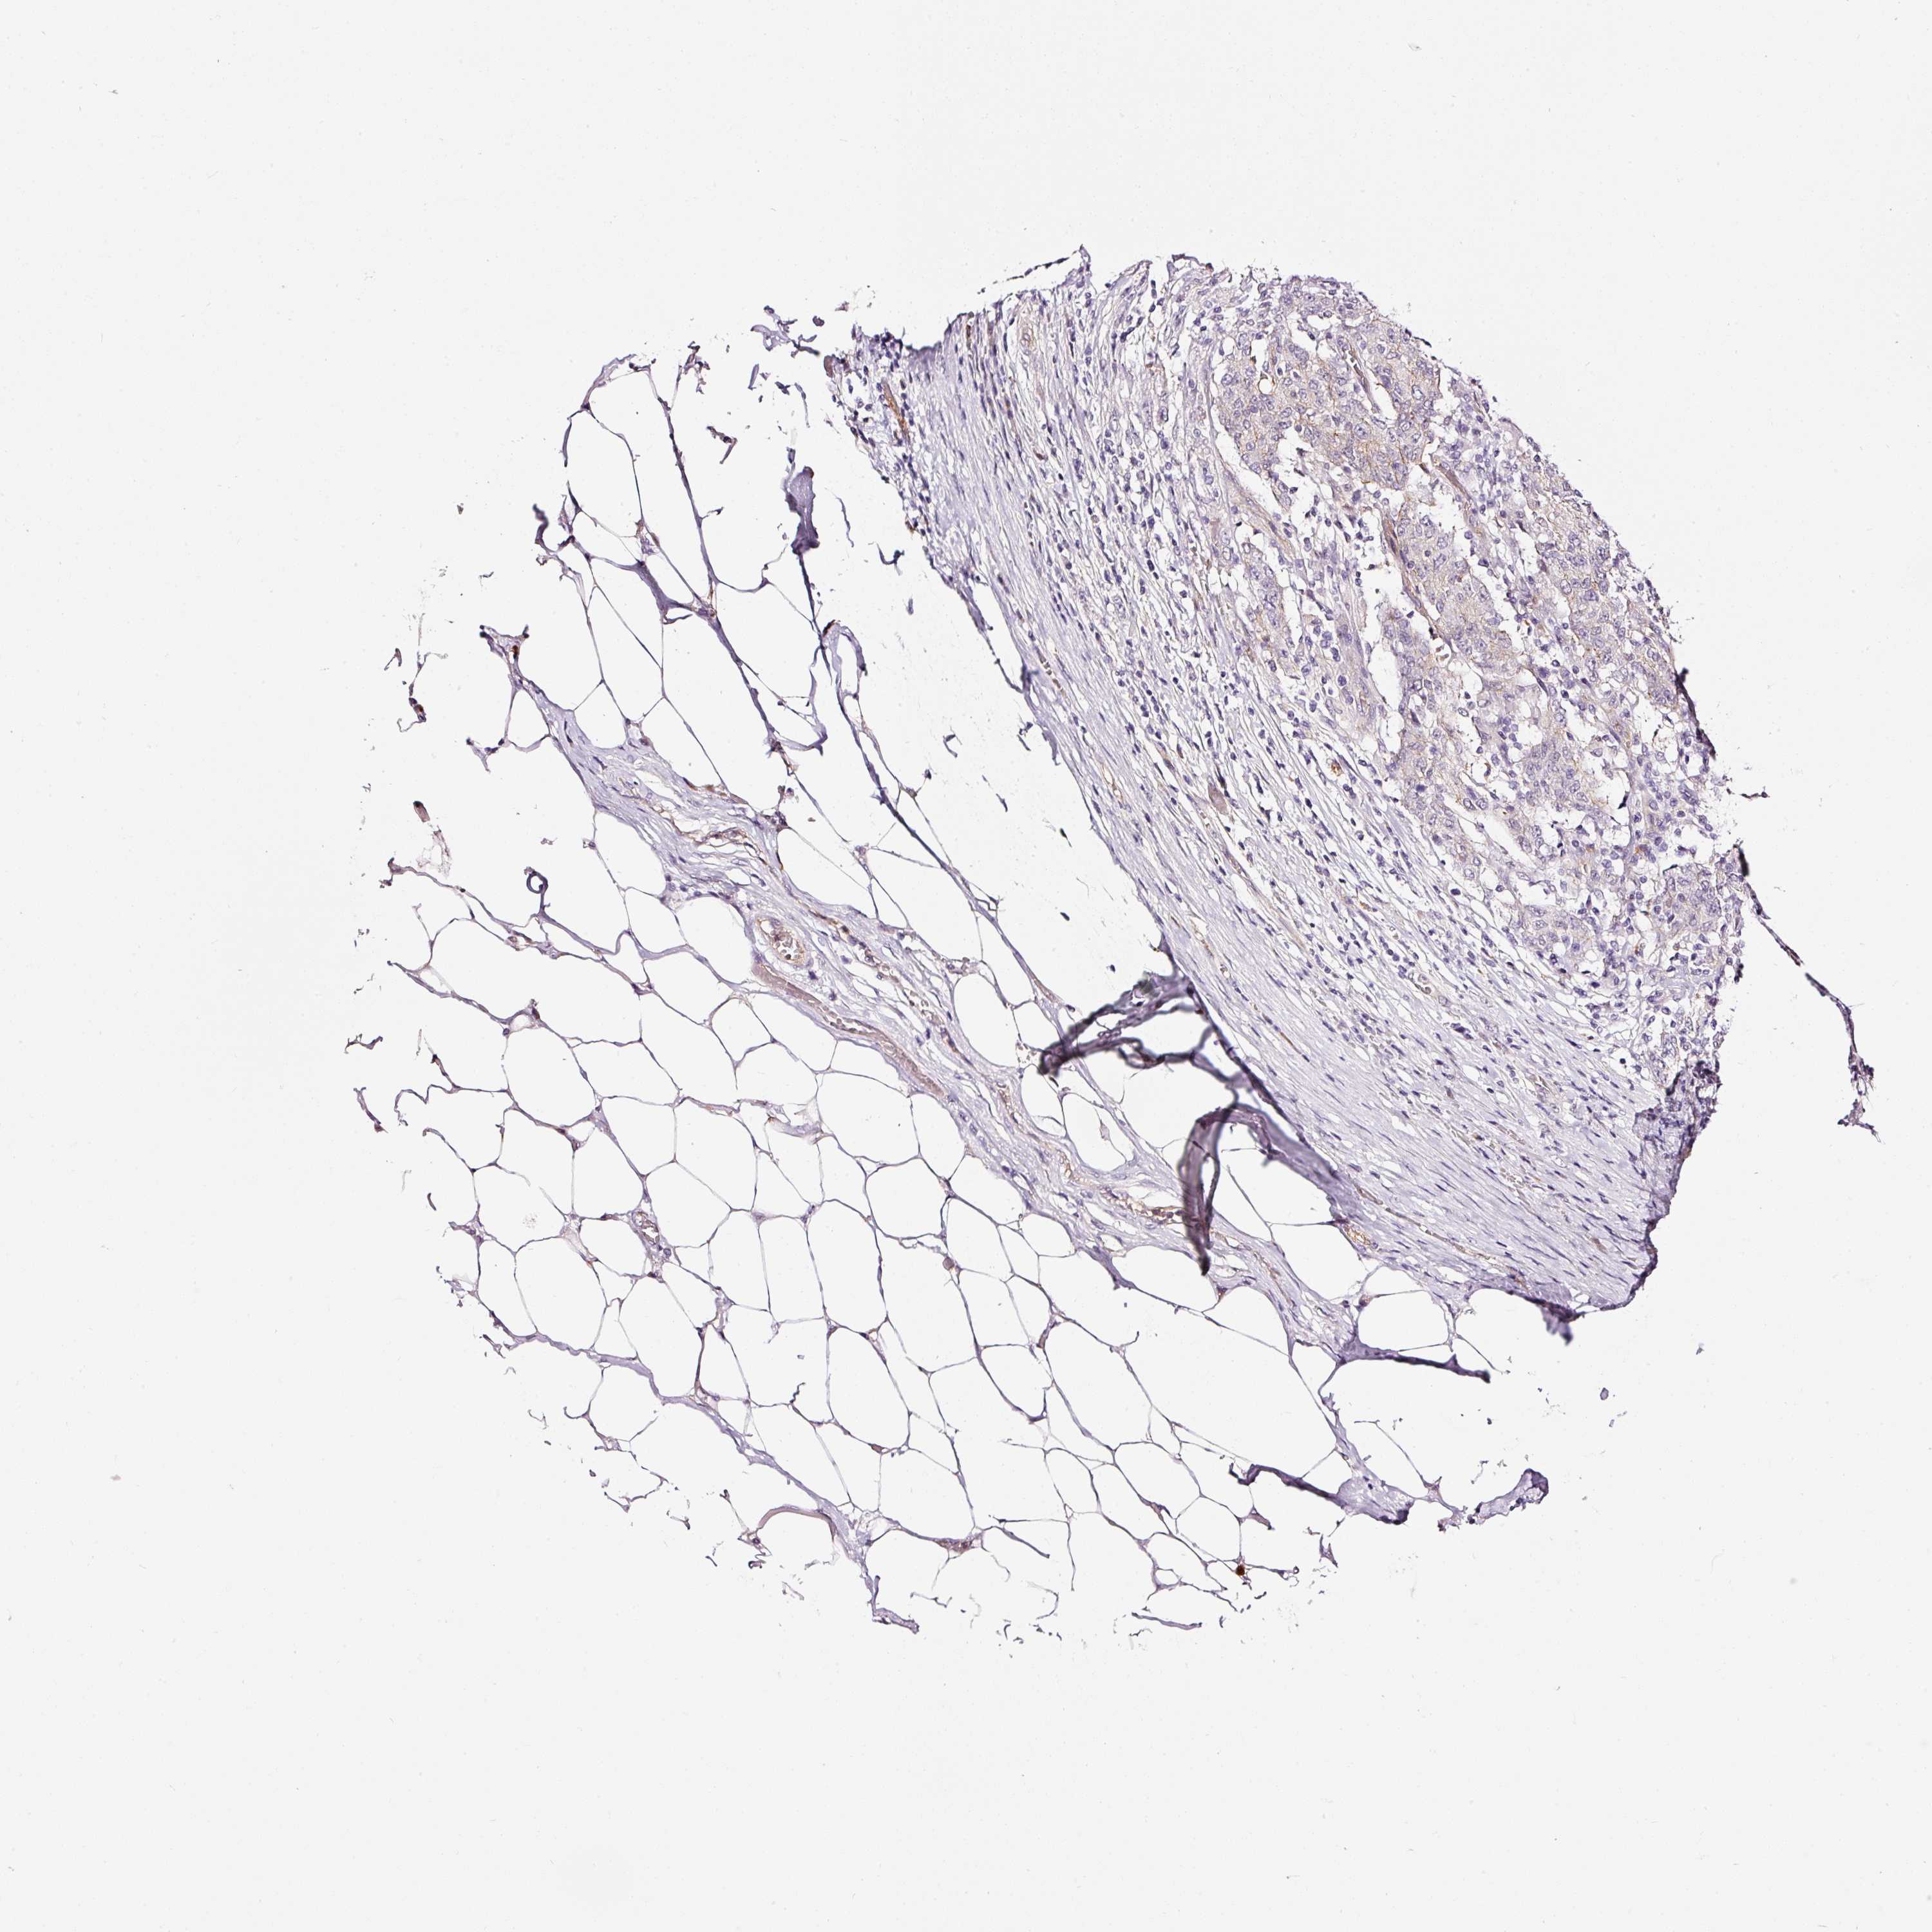

STOMACH CANCER - Protein expressioni

A mouse-over function shows sample information and annotation data. Click on an image to view it in a full screen mode. Samples can be filtered based on level of antibody staining by selecting one or several of the following categories: high, medium, low and not detected. The assay and annotation is described here.

Note that samples used for immunohistochemistry by the Human Protein Atlas do not correspond to samples in the TCGA dataset.

Antibody stainingi

Antibody staining in the annotated cell types in the current human tissue is reported as not detected, low, medium, or high, based on conventional immunohistochemistry profiling in selected tissues. This score is based on the combination of the staining intensity and fraction of stained cells.

Each image is clickable and will lead to virtual microscopy that enables deeper exploration of all samples and also displays staining intensity scores, fraction scores and subcellular localization as well as patient and tissue information for each sample.

Antibody HPA049395

Antibody HPA053288

Staining

High

Medium

Low

Not detected

Adenocarcinoma, NOS